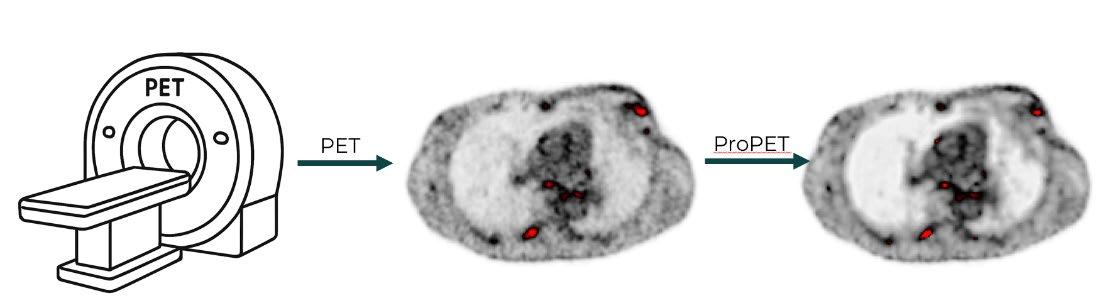

Project Title: Quantifying the Specificity of MLBased ProPET for Small Lesion Detection

The Machine Learning based ProPET methodology has demonstrated increased sensitivity, better contrast, and reduced noise in PET imaging. However, enhanced sensitivity could potentially lead to false-positive lesion detection, particularly for small structures.

This project will quantify the specificity of ML-based ProPET for detecting small high-activity regions simulating cancer. The student will insert synthetic lesions of varying sizes (3-15 mm) and activity levels (SUV 2-8) into healthy patient PET data, apply standard reconstruction and ML-based ProPET, and quantify specificity and false-positive rates.

Key metrics include specificity/sensitivity as function of lesion size, false-positive rate in known healthy regions, and ROC curves compared to standard methods.